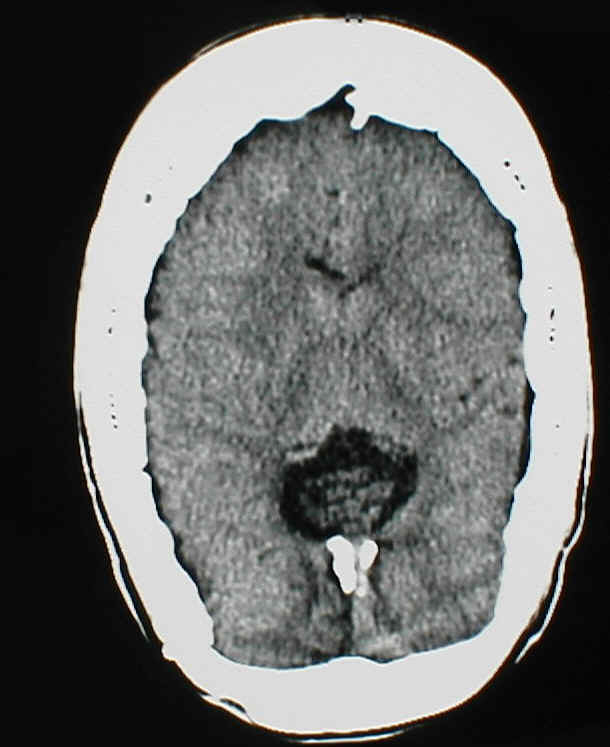

wie unter 4. Slit ventricle Syndrom erwähnt, kann es im Rahmen einer chronischen Überdrainage zum Verstopfen des Ventrikelkatheters kommen. Das Bild unten zeigt eine solche Komplikation. Unschwer erkennt man auf dem CT (rechts) die schlitzförmigen Ventrikel und dass der Ventrikelkatheter praktisch vollständig von Hirngewebe umschlossen ist. Die Folge ist auf dem linken Bild deutlich zu sehen. Die Löcher des Katheters und auch weitere Anteile des Shunts sind mit Gewebe verstopft. Dieser Shunt kann nicht mehr funktionieren.